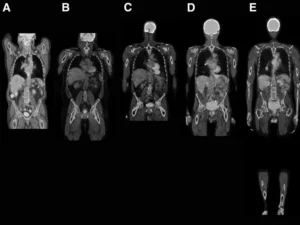

Tüm vücut MR, manyetik rezonans görüntüleme teknolojisi kullanılarak vücudun tamamının ayrıntılı bir şekilde taranmasıdır. Radyasyon içermeyen bu yöntem, manyetik alan ve radyo dalgaları yardımıyla organların ve dokuların yapısını detaylı bir şekilde gösterir. Doktorlar, bu görüntüleri kullanarak hastalıkları teşhis eder ve tedavi planlarını oluşturur.

Tüm vücut MR, genellikle hastalıkların erken teşhisi ve yayılımının değerlendirilmesi amacıyla çekilir. Özellikle kanser taramaları, inflamatuar hastalıklar, enfeksiyonlar ve dejeneratif hastalıkların tespitinde kullanılır. Ayrıca, vücutta mevcut olan anormalliklerin detaylı bir şekilde incelenmesi için de tercih edilir.

Tüm vücut MR ile kanser türleri, tümörlerin yayılımı, inflamatuar hastalıklar, enfeksiyonlar, dejeneratif hastalıklar, sinir sistemi bozuklukları ve damar hastalıkları teşhis edilebilir. Bu yöntem, özellikle erken teşhis gerektiren hastalıklarda büyük önem taşır ve doktorların doğru tedavi yöntemini belirlemelerine yardımcı olur.